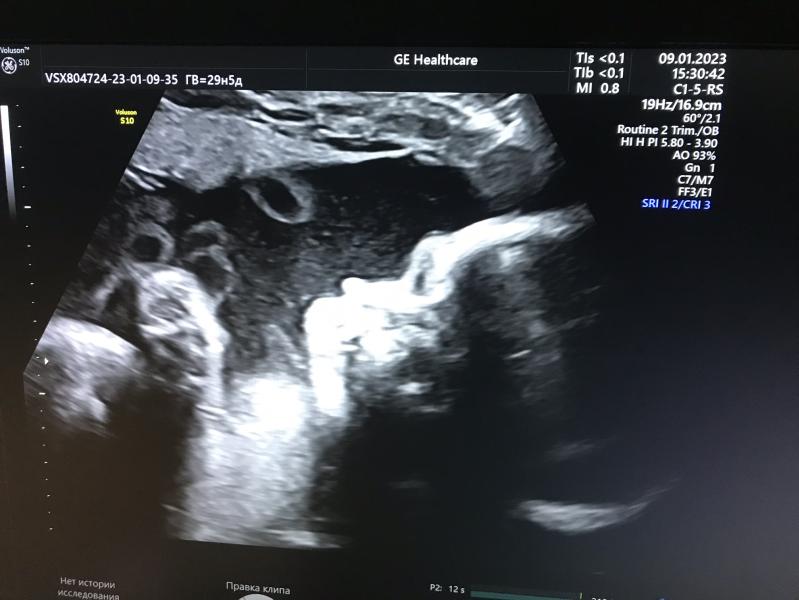

Сходила на 3 узи сказали все хорошо

Вес 1404гр,

Срок: 29 недель и 5 дней

Околоплодные воды в норме

Хочу здесь оставить фото ее 🥰🥰🥰